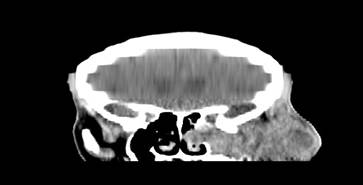

La TAC evidenció masa heterogénea a nivel del seno maxilar, destrucción ósea de la pared lateral del seno, piso de la órbita y arco cigomático, además se observó extensión hacia partes blandas de la región temporo-parietal izquierda (Figura 3 y 4).

Las imágenes de seno maxilar ocupado por masa de aspecto tumoral con compromiso de estructuras óseas vecinas (observadas en la TAC) y el análisis histológico fueron determinantes para el diagnóstico de carcinoma epidermoide de seno maxilar. Llegar a este resultado por lo general es tardío porque los signos y síntomas son inespecíficos. La relación de proximidad del seno maxilar con la base de cráneo, órbita, cavidad nasal, seno esfenoidal, seno etmoidal y el frontal hacen que la planificación del tratamiento sea compleja.